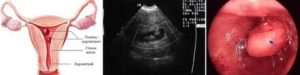

Анатомия матки

Матка — орган репродуктивной системы женского организма, в котором зарождается и развивается плод. Располагается в полости малого таза между мочевым пузырем и прямой кишкой. По этой причине выделяют пузырную (переднюю) и кишечную (заднюю) поверхности матки.

Диагноз «гиперплазия эндометрия» ставится при разрастании внутреннего слоя матки до 15 мм и более. Ультразвуковое обследование может выявить заболевание, однако природа его может быть определена только при непосредственном изучении клеток слизистой.

Гистероскопия и РДВ

В настоящее время РДВ производится в комплексе с гистероскопией.

Гистероскопия матки – визуальный метод диагностики внутренней полости органа при помощи оптического аппарата – гистероскопа. Возможности гистероскопа позволяют врачу визуально определить состояние полости матки, с большей точностью производить определенные манипуляции в ходе операции по выскабливанию, оценить результат операции.